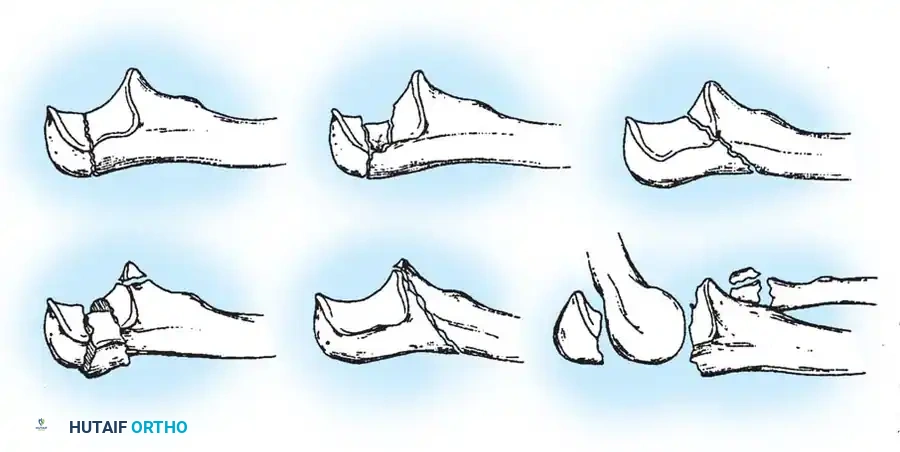

Schatzker classified olecranon fractures based on the fracture pattern and the mechanical considerations dictating the required type of internal fixation. Understanding this classification is paramount for preoperative planning.

Fig. 54-52 A-F, Schatzker classification of olecranon fractures. (From Browner BD, Jupiter JB, Levine AM, et al, eds: Skeletal trauma, Philadelphia, Saunders, 1992.)

The Schatzker classification includes:

* Transverse: Typically avulsion injuries amenable to tension band wiring.

* Transverse-Impacted: Requires elevation of the impacted articular segment and bone grafting before fixation.

* Oblique: May require lag screw fixation in addition to a neutralization plate or tension band.

* Comminuted: High-energy injuries often requiring plate osteosynthesis to prevent shortening of the greater sigmoid notch.

* Oblique-Distal: Fractures extending distal to the coronoid process, compromising elbow stability.

* Fracture-Dislocation: Complex injuries requiring rigid plate fixation to restore the stabilizing buttress of the proximal ulna.